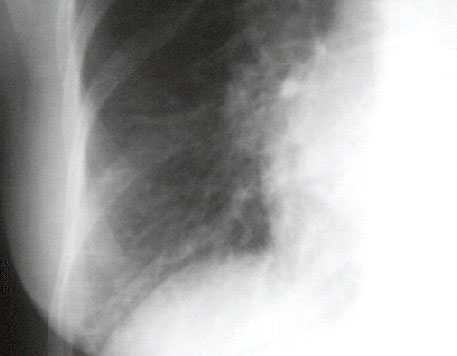

In this enlargement of the right lower lung field, so-called Kerley B lines are seen. They are due to lymphatic engorgement, and imply a significantly elevated left atrial pressure.